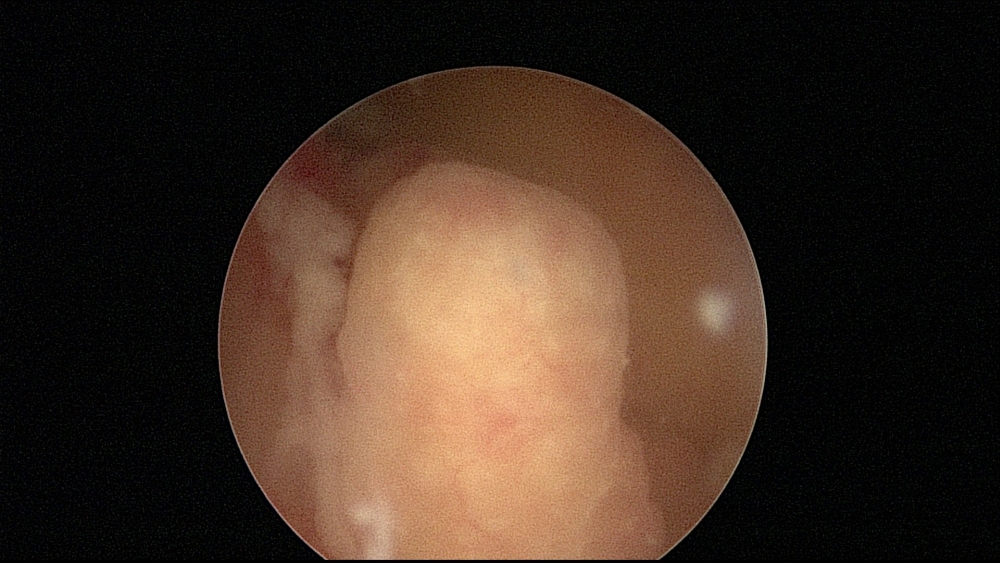

Histeroskopia jest endoskopową metodą diagnostyczno-terapeutyczną, umożliwiającą obrazowanie wnętrza kanału szyjki i jamy macicy oraz równoczasowe leczenie stwierdzonych tam nieprawidłowości.

Histeroskop składa się z 2 płaszczy i teleskopu sprzężonego z kamerą, przekazującą obraz na monitor. Pod płaszczem zewnętrznym przepływa podawany przez specjalną pompę płyn dystensyjny, którego zadaniem jest rozszerzenie jamy macicy i usuwanie zanieczyszczeń pojawiających się w polu widzenia. W obrębie płaszcza wewnętrznego znajduje się kanał roboczy dla narzędzi operacyjnych.